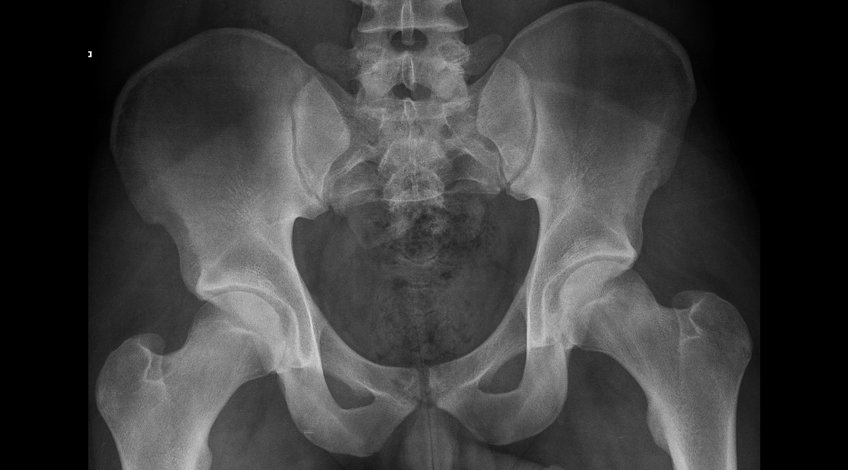

Radiografías, Imagenes de Pelvis

Una radiografía de pelvis es una prueba segura e indolora que usa pequeñas cantidades de radiación para tomar imágenes de los huesos pélvicos, que están alrededor de la zona de la cadera. La pelvis conecta las piernas con el cuerpo.

Se suele tomar una o dos imágenes de la pelvis, una con las piernas estiradas y desde una vista anteroposterior y una segunda con las piernas flexionadas desde una vista lateral. Las imágenes se toman mientras el paciente está acostado sobre la espalda. Es posible que deba mover su cuerpo a otras posiciones para proporcionar diferentes puntos de vista.

Las imágenes que se obtienen son en blanco y negro. Las partes densas del cuerpo, que bloquean el paso de los rayos X, como los huesos, aparecen en color blanco en la radiografía.